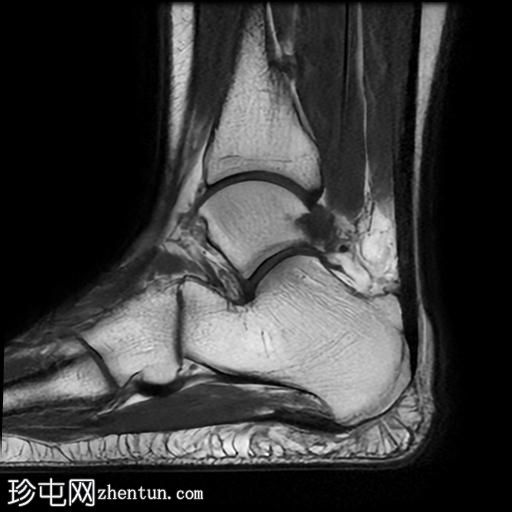

矢状位

T1加权像

矢状位PD加权像

脂肪抑制像

足底筋膜附着处可见足底跟骨骨刺,伴有下方局灶性骨髓水肿。

足底筋膜跟骨起点处可见增厚,并伴有实质内液体信号增高,尤其是在中内侧纤维,提示足底筋膜炎。

足底筋膜炎是指足底筋膜的炎症,是足跟痛最常见的原因。该病常伴有足底筋膜附着于跟骨处的骨刺,这会加重症状的严重程度并延长病程。